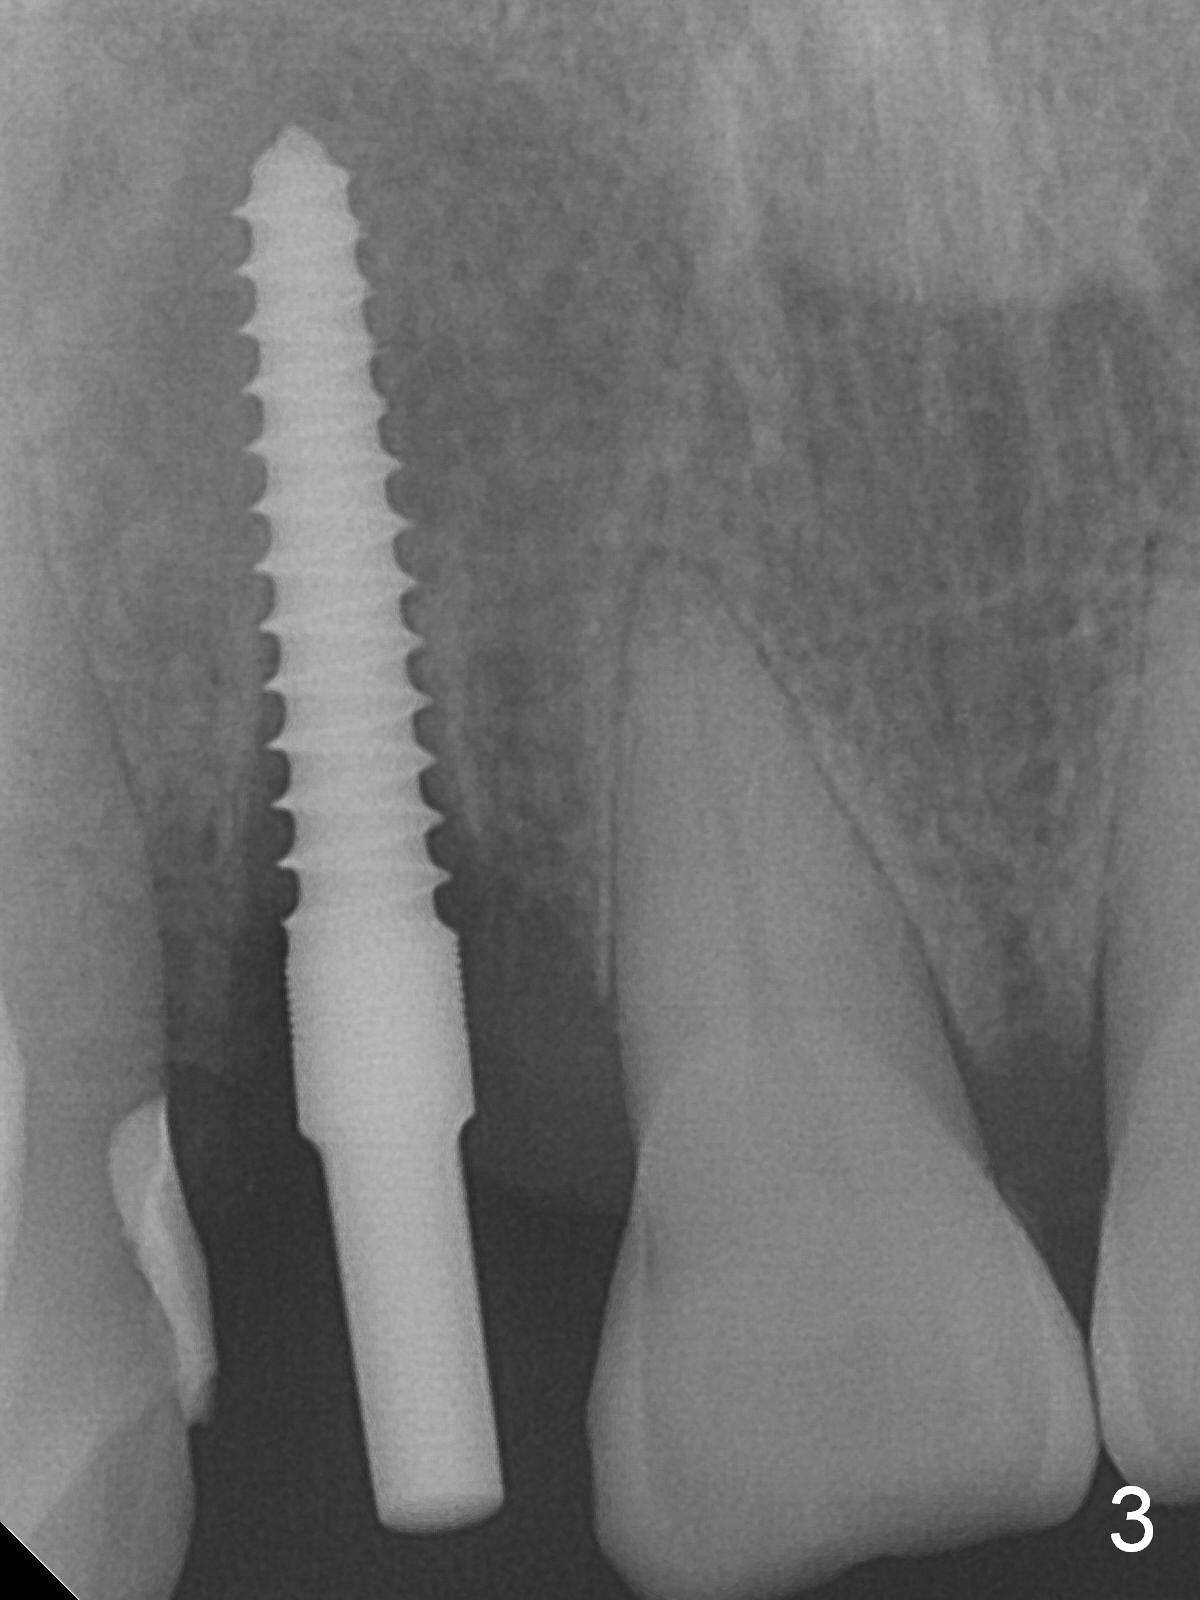

When the flaps are raised, the buccal plate is found to be perforated (Fig.2 *); osteotomy is being established in the narrow palatal wall (<). When a 3x17 mm (tissue-level) 15 ° 1-piece implant is placed (Fig.3,5 P), the incisal end of the implant is between the incisal edge of the central incisors and that of the tooth #10 (Fig.6) so that the temporary crown (Fig.7 T) is slightly buccal with sufficient palatal clearance with the opposing dentition.